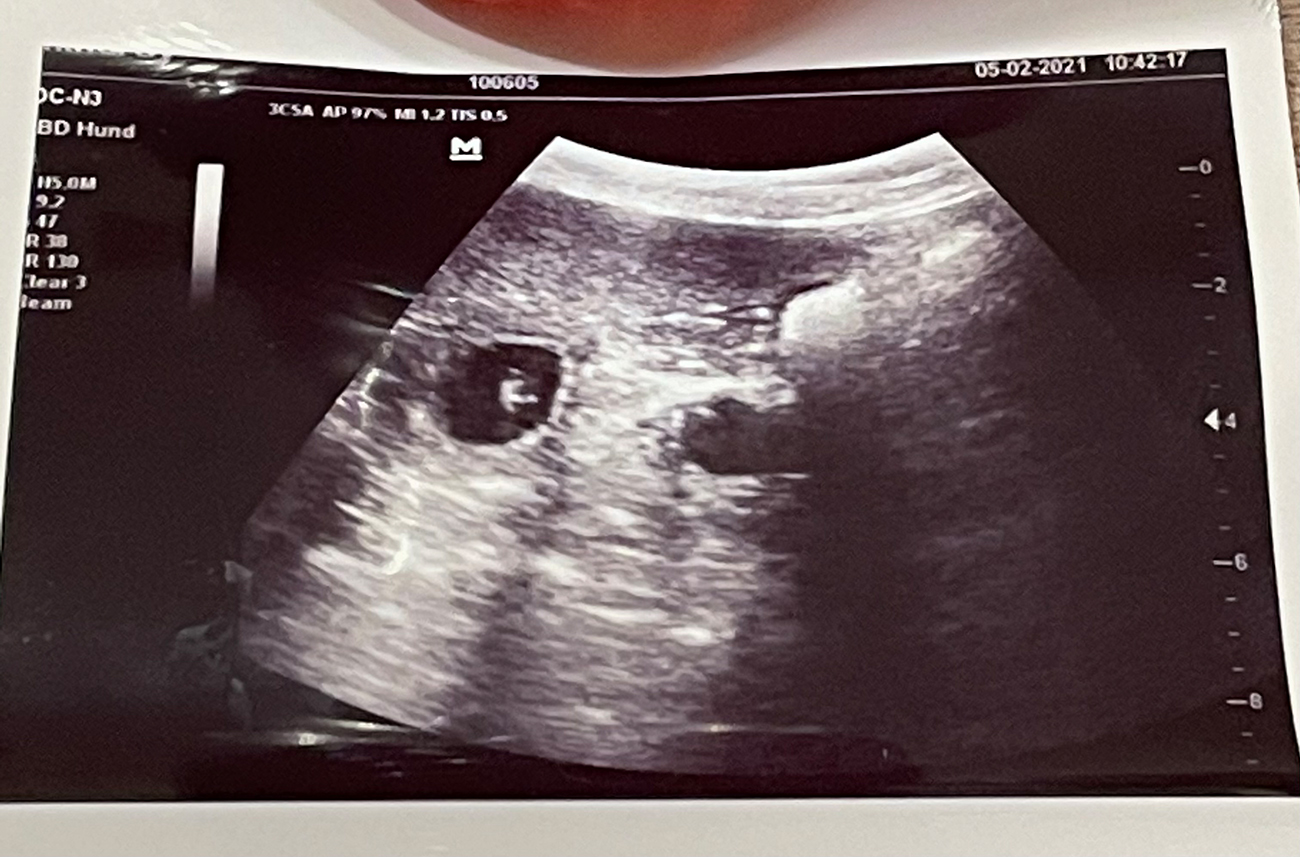

Heute war also der Tag der Tage. Der Tag an dem man Gewissheit bekommt, ob die Hündin aufgenommen hat oder nicht.

Auch wenn in den letzten Tagen einiges für eine Trächtigkeit gesprochen hat, so wollten wir es gerne

von unserem Tierarzt Dr. Marcus Stieger absegnen lassen.

Beim Ultraschall wurden auf Anhieb einige Fruchtanlagen gesichtet. Die genaue Anzahl wollte ich aber nicht wissen.... ein bisschen Spannung soll uns und den Welpeninteressenten schon noch in den kommenden Wochen erhalten bleiben. ;-) |

Wir freuen uns einfach riesig darüber, dass bald wieder kleine J-Racker den Bagalutenhof besetzen werden.